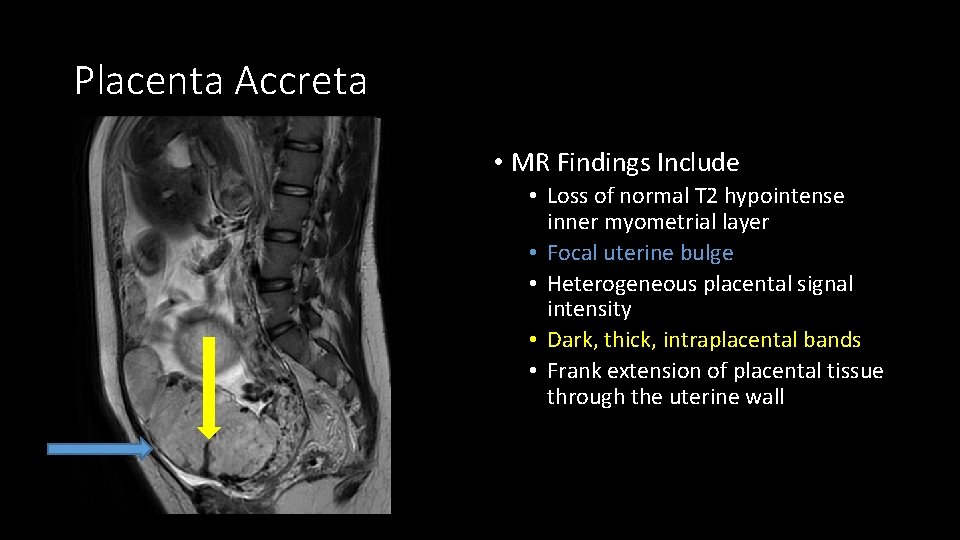

Placenta Accreta • MR Findings Include • Loss of normal T 2 hypointense inner myometrial layer • Focal uterine bulge • Heterogeneous placental signal intensity • Dark, thick, intraplacental bands • Frank extension of placental tissue through the uterine wall